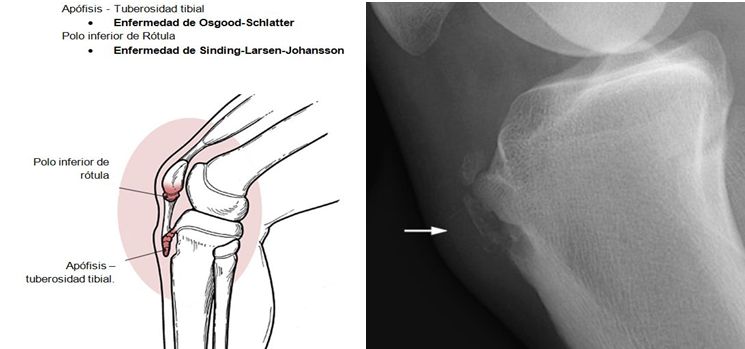

DOLOR EN MIEMBROS INFERIORES.

SEMIOLOGIA DE LOS MIEMBROS INFERIORES